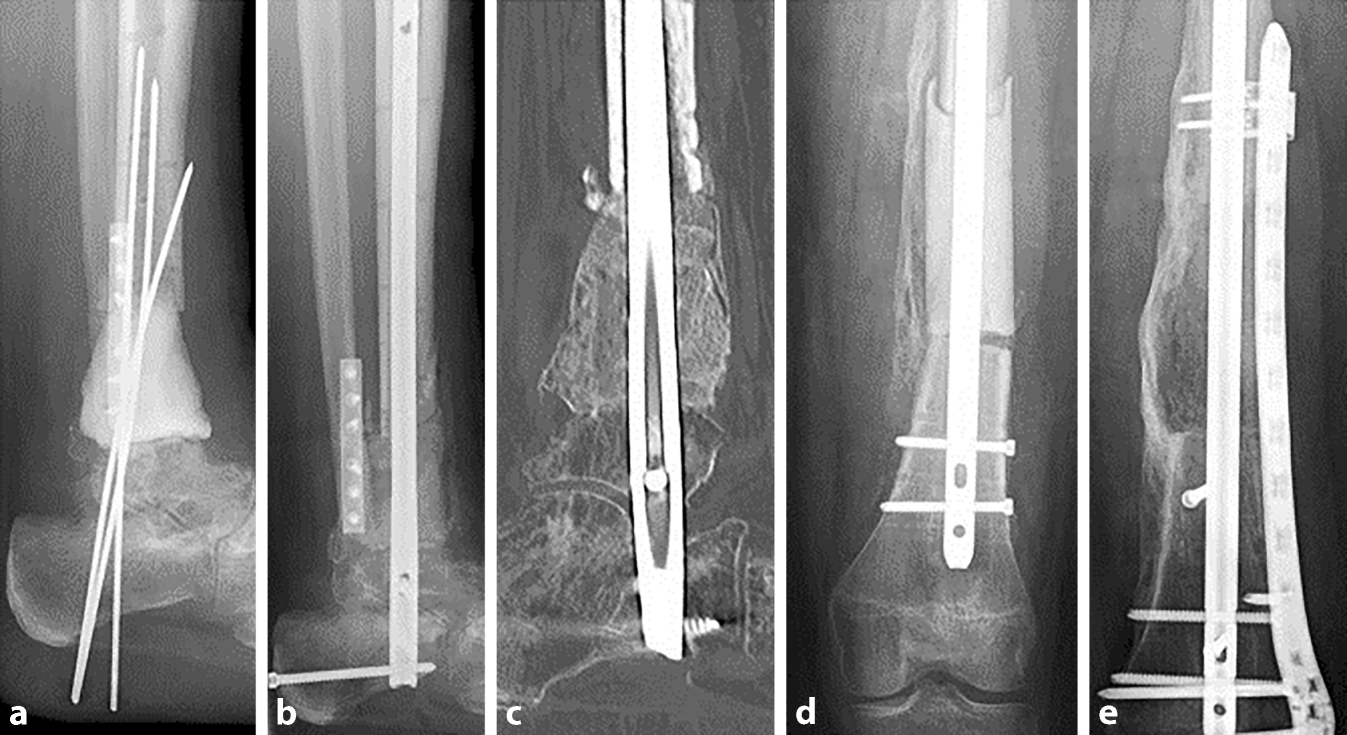

Abb. 1

a,b Repositionsverlust und Sedimentationseffekt einer MT durch RIA und Ringfixateur; c Materialentfernung, Entfernung der Masquelet-Plastik und des avitalen Knochens, erneutes Einbringen eines Spacers ohne temporäre Osteosynthese; d,e MT durch zwei dekortizierte Femurköpfe und RIA, Doppelplattenosteosynthese, die Röntgenkontrolle nach zwei Monaten zeigt bereits eine Konsolidierung

Absolute Stabilität von Osteosynthese und Masquelet-Plastik sind die Voraussetzungen einer erfolgreichen Therapie. Liegen Defekte im Isthmusbereich langer Röhrenknochen vor, kann die Osteosynthese mit einem ausreichend starken Nagel genügen. Liegt keine ausreichende Stabilität vor, sollten zusätzlich winkelstabile Platten verwendet werden (Abb. 2e, 3d und 4b). Im Gelenkbereich werden typischerweise winkelstabile Doppelplattenosteosynthesen angewandt (Abb. 1d, e).